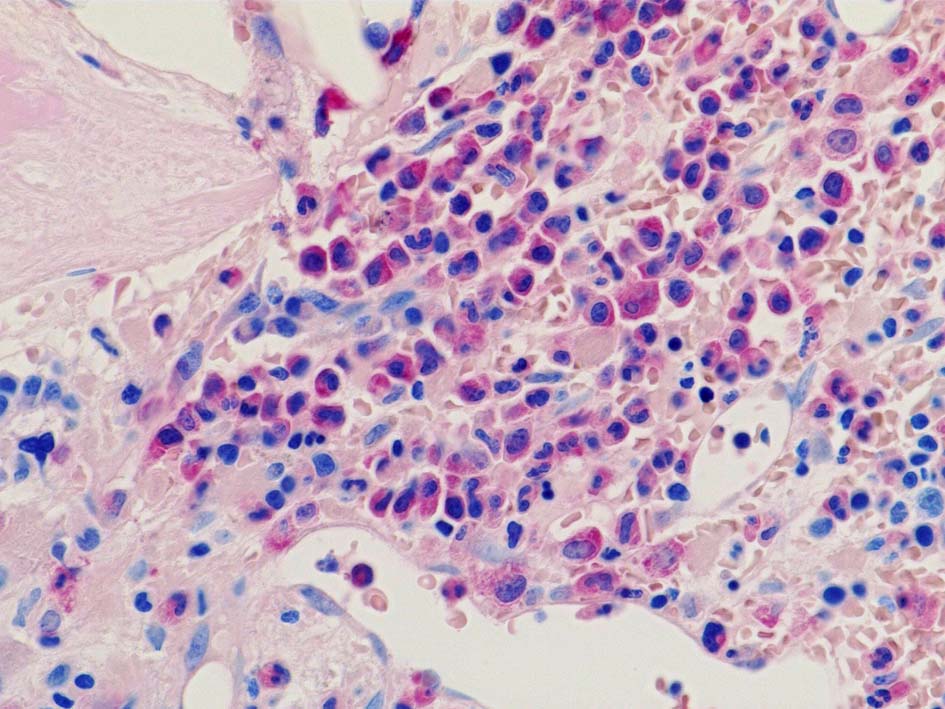

骨髄組織所見 bone marrow biopsy total 6mm in length

CD42b染色